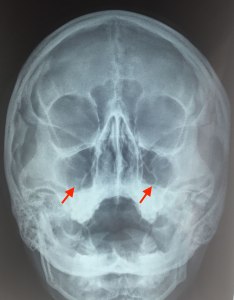

3. В то время как мозг тоже обладает чувствительностью к радиации, но он защищен черепной коробкой, которая обеспечивает ему дополнительную защиту. Поэтому нет необходимости в специальной защите головы от рентгеновского излучения.